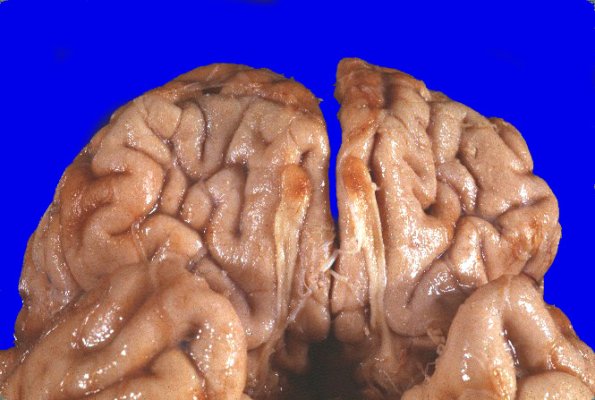

There are numerous foci of orange-brown discoloration and surface granularity involving the tips of the occipital lobes, the right cerebellum, anterior frontal lobes, particularly the inferior orbital aspects and involving the olfactory bulbs, as well as the lower lateral aspects of the frontoparietal cortices bilaterally. The right cerebellar hemisphere is markedly shrunken, particularly the superior aspect. All the hemorrhagic lesions were thought to represent contusions.